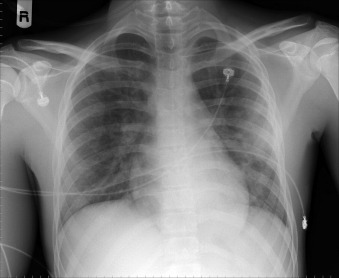

Of all traumatic lesions to the thoracic cardiovascular system, the most predictable one is blunt deceleration/acceleration traumatic injury to the thoracic aorta, resulting in a false aneurysm-type lesion, typically of the isthmus proximal descending aorta. It may also involve the ascending aorta, the supradiaphragmatic aorta, or the innominate artery take-off ( Figs. 28-1 to 28-13 ).